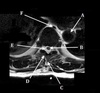

19

Q

What is letter A?

A

20

What is letter B?

21

What is letter C?

22

What is letter D?

23

What is letter E?

24

What is letter F?

25

What is letter H?

SUPRASTERNAL NOTCH

27

DESCENDING THORACIC AORTA

SPINOUS PROCESS

30

LAMINA

31

CSF

32

AZYGOS VEIN